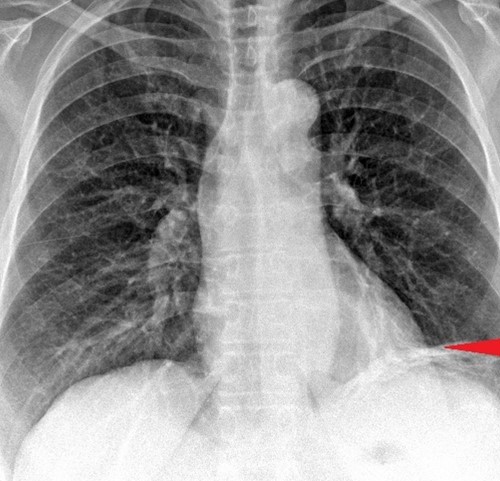

Contrast-enhanced CT of the abdomen, revealing air in intrahepatic biliary tree (pneumobilia) (red arrow)